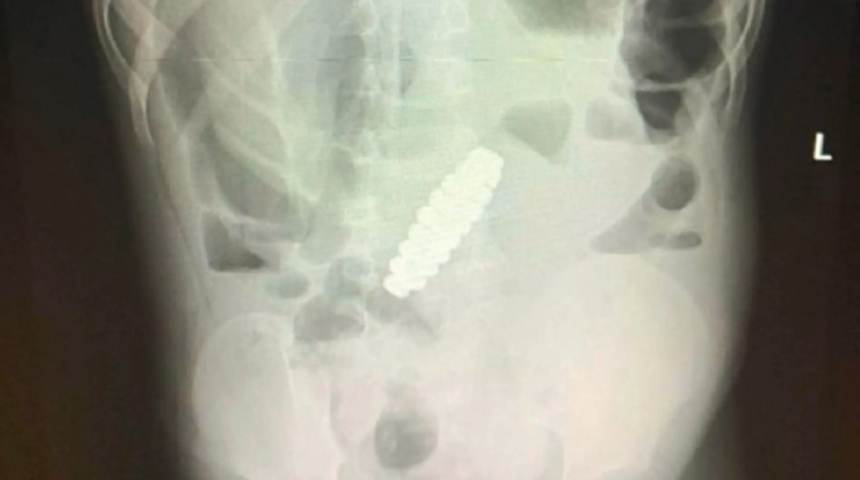

Semptomları iki gün sonra hala azalmadığında, doktorlar neyin yanlış olduğunu görmek için bir ultrason yaptılar. İşte o zaman çocuğun acısının şaşırtıcı nedenini keşfettiler: Çocuğun midesinde bir bilezik vardı. Eşlik eden röntgenler, çocuğun karın boşluğuna yerleştirilmiş opak bir boncuk halkasını gösteren yabancı cismi gösterdi. Ebeveynler, oğullarının olağandışı bir şey yuttuğunu görmedikleri için doktorlar kadar şaşkındı.

Daha da kötüsü, vücuda sızan önemsiz şey çocuğun bağırsaklarını tıkıyor ve hatta bağırsaklarında delikler açıyordu. Daha fazla hasarı önlemek için doktorlar acil bir laparotomi - cerrahların karın boşluğunda bir kesi yaptıkları bir ameliyat - gerçekleştirdiler ve 18 altıgen şekilli manyetik boncuktan oluşan bileziği çıkardılar. Çocuğun bağırsak duvarındaki delikleri de onardılar.